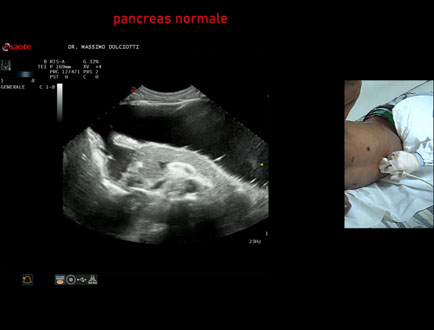

Data inserimento: 22/12/2023

Ecografia del: 30/11/2023

Strumento: Esaote MyLab Eight

Sonda: Convex Multifrequenza 1-8 MHz

Età Paziente: M 33 anni

Motivazione dell'esame: litiasi della colecisti.

Commento all'esame: le immagini ed il video documentano il fegato normale - segmentazione epatica, pancreas normale, colecisti con piccolo calcolo.

Conclusioni: segmentazione epatica, pancreas e colecisti con piccolo calcolo (liver segmentation, pancreas and gallbladder with small stone).

Presentazione: Dr. Massimo Dolciotti - Ancona

Elaborazione digitale: Andrea Dini - Ancona